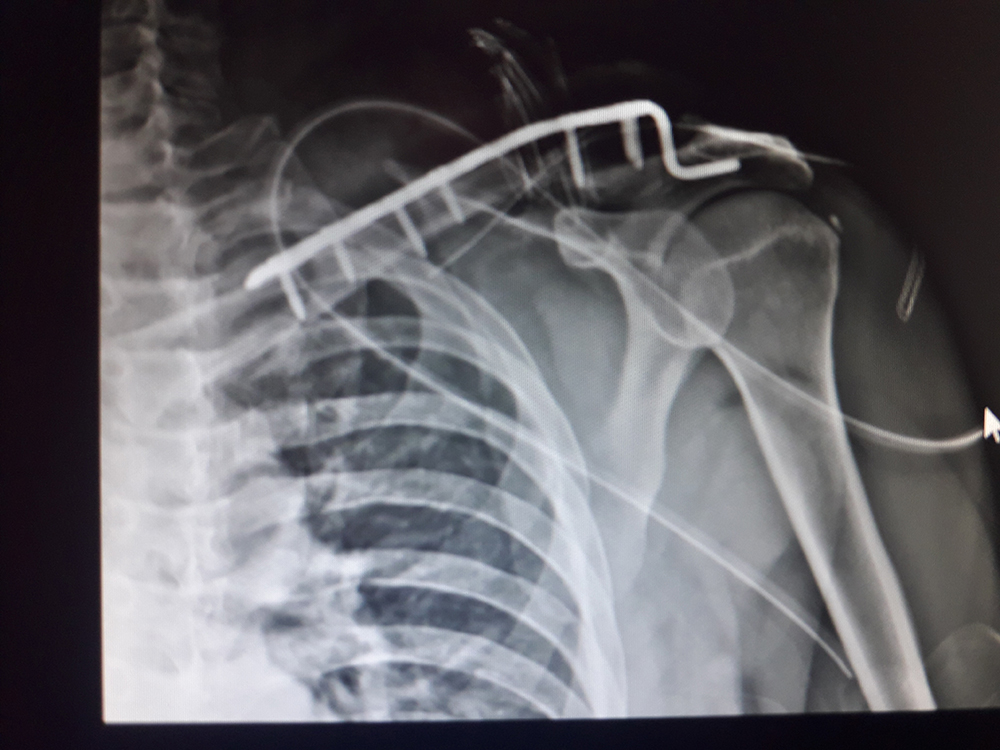

Zabiegi

Moja praca w RTG